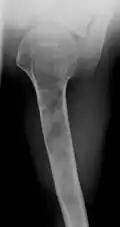

Enchondromas localized in the upper part of the humerus of the same patient

-

X-ray showing calcified enchondromas localized in finger a 37-year-old patient affected with Ollier disease -

X-ray showing enchondromas localized in the humerus of a 37-year-old patient affected with Ollier disease -

X-ray showing enchondromas localized in the lower part of the radius of a 37-year-old patient affected with Ollier disease -